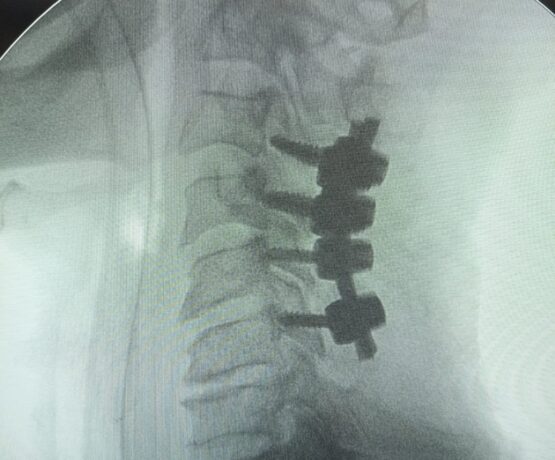

Lminectomy C3 down to C6 augmented by lateral mass fixation

Male 55 year daibetc known CSM operated 5 years by C5 C4 lamenectomy Pre operative Presented by progressive mylopathy VAS neck pain 8JOA score 9Preoperative…